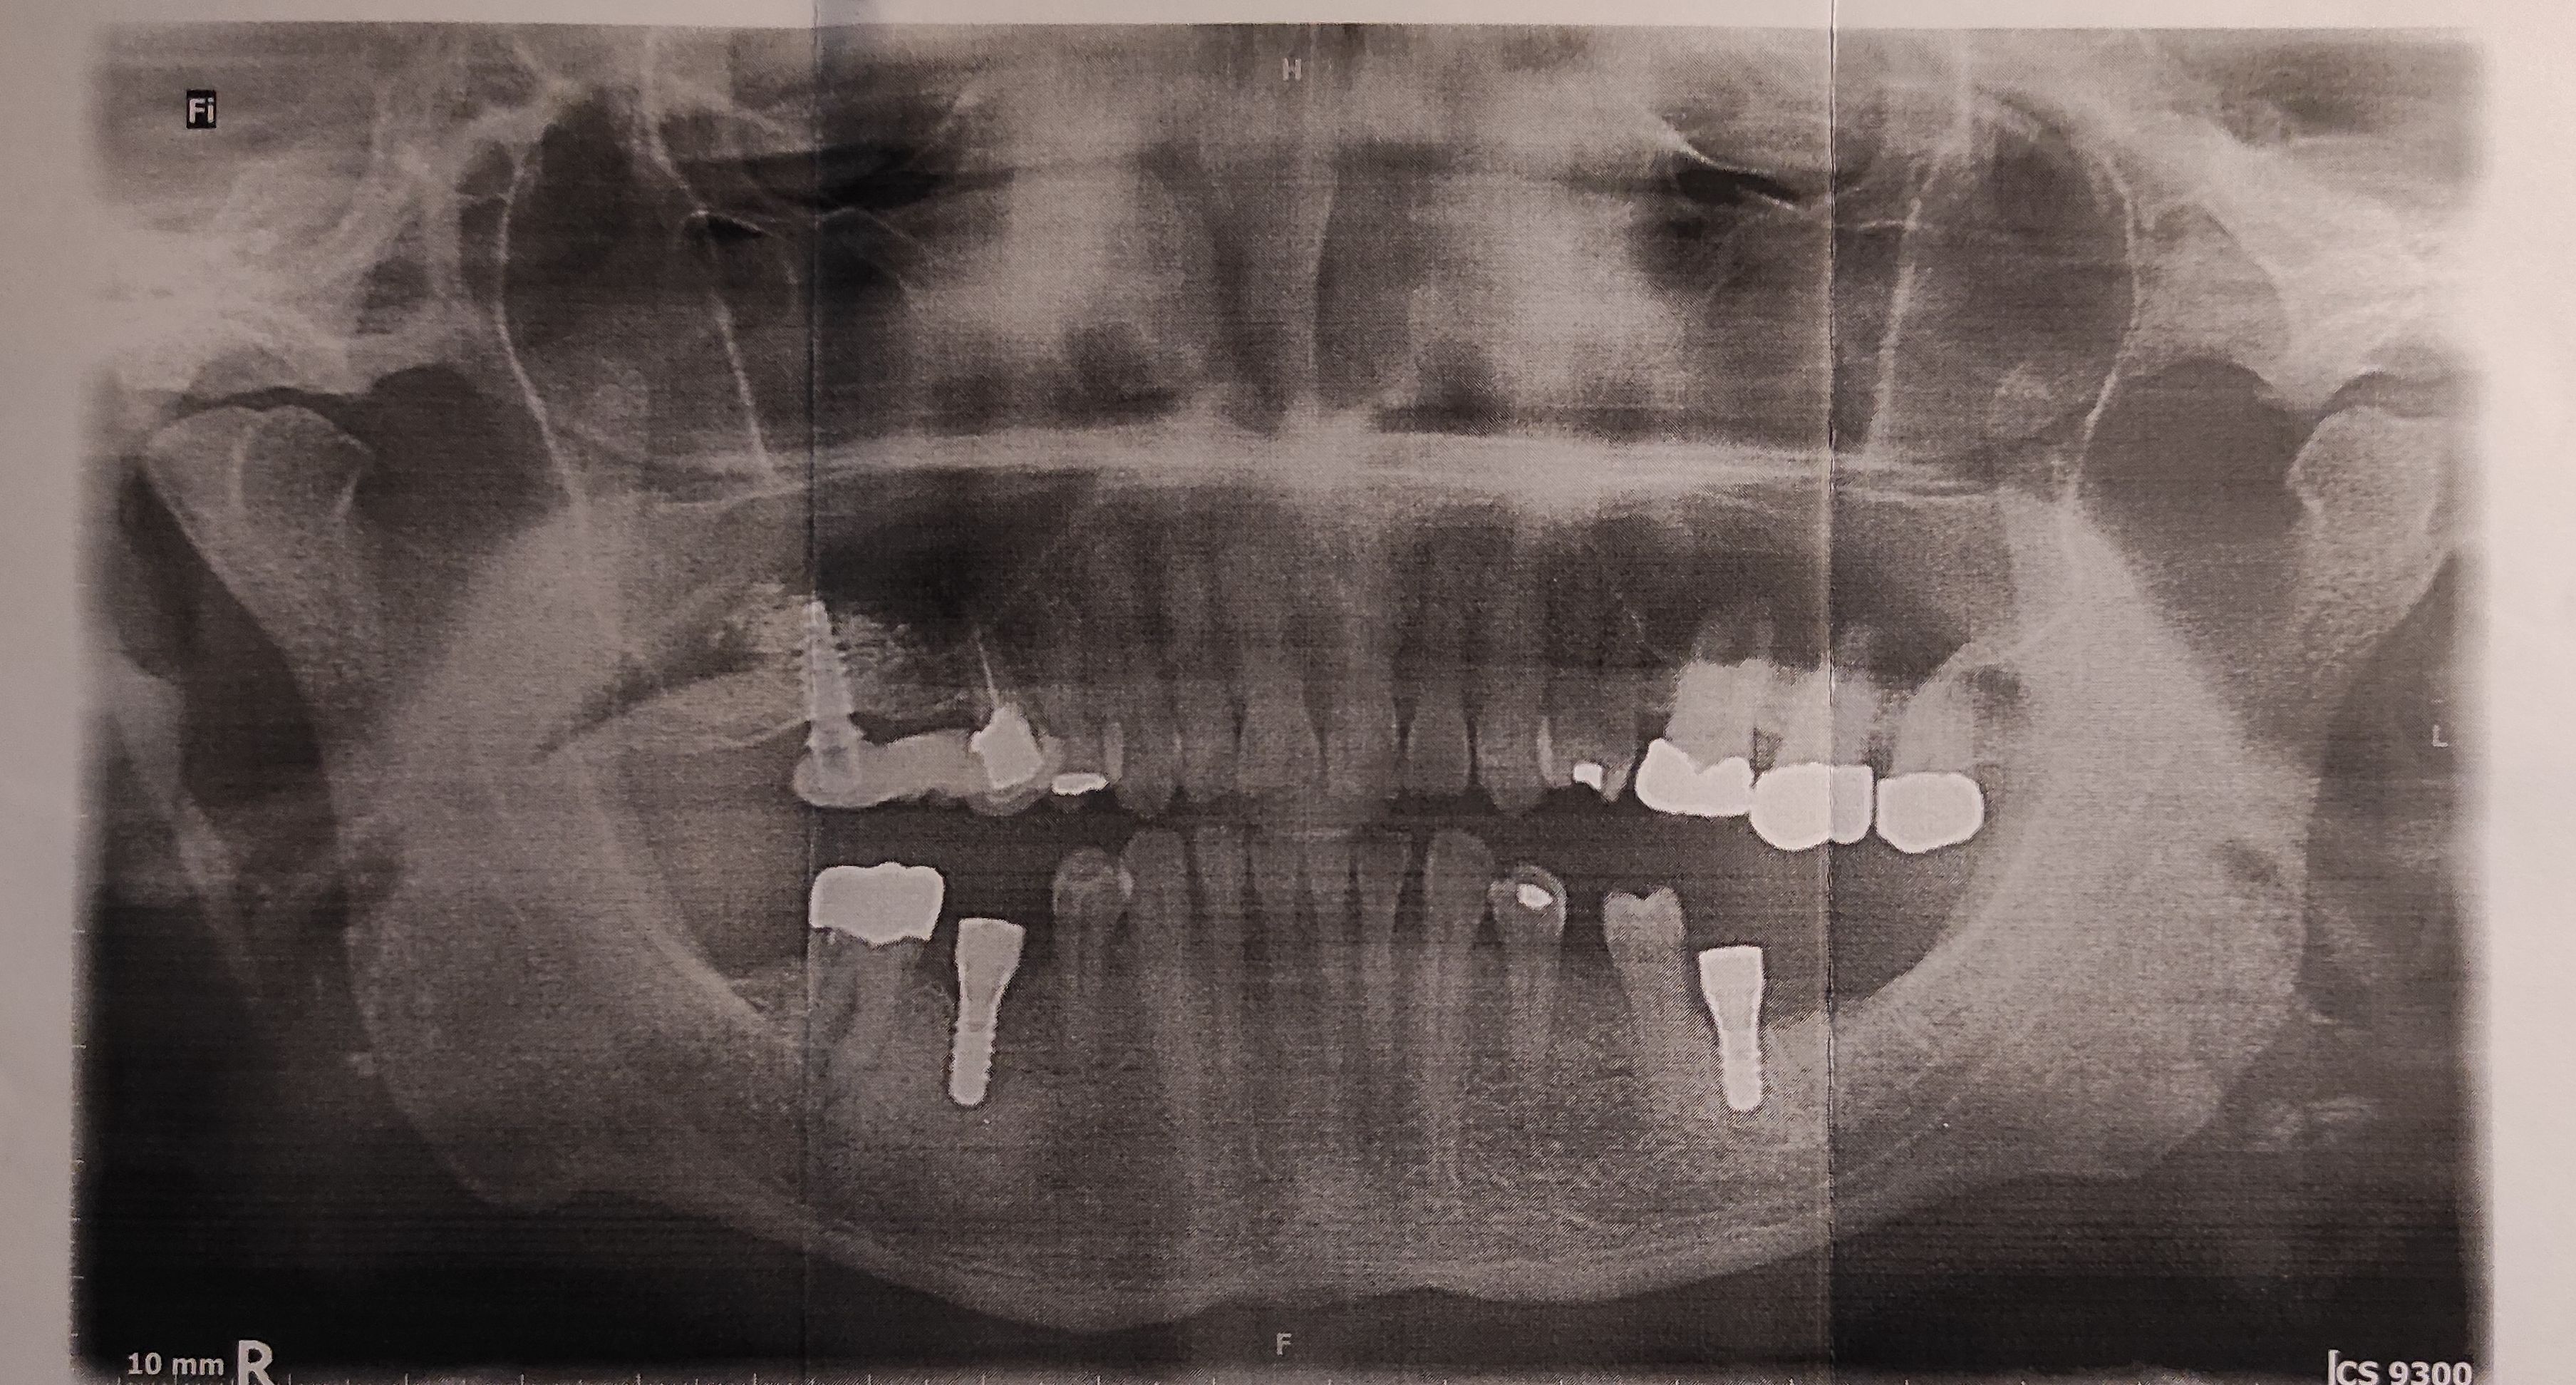

• Implantate bereits vorhanden: Regio 36, 46

• Implantathersteller: Straumann

• Implantate wurden gesetzt: 17.06.25

1.) Mir wurden 2 Implantate in den UK eingesetzt. Die Arbeiten wurden am 13.10.2025 abgeschlossen. Ein Röntgenbild nach Abschluss wurde beigefügt. Ebenso die Kopie des Implantat-Ausweises. Die Bezahlung wurde auschließlich von mir übernommen (d. h. keine PKV).

2.) Somit geht es hierbei nur noch um das Einsetzen der zwei (Verblend-) Kronen.

Auf meine zwei Implantate im Unterkiefer (eines rechts, eines links) sollten Kronen aufgesetzt werden. Die Implantate wurden in einer anderen Praxis eingesetzt. Die Kosten für die implantatgestützten Kronen empfand ich allerdings als sehr hoch. Daher habe ich die Auktion auf 2te-Zahnarztmeinung gestartet.